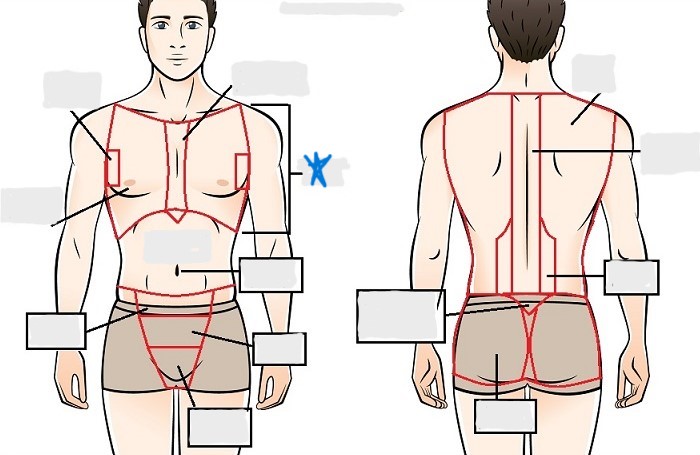

axial

cephalic

occipital

frontal

otic

orbital

nasal

oral

mental

cervical

dorsal

scapular

vertebral

lumbar

sacral

gluteal

thoracic

sternal

mammary

axillary

abdominal

umbilical

pelvic

inguinal

pubic

perineal

appendicular

acromial

brachial

antecubital

olecranal

antebrachial

carpal

manus

coxal

femoral

patellar

popliteal

crural

sural

peroneal

calcaneal

plantar